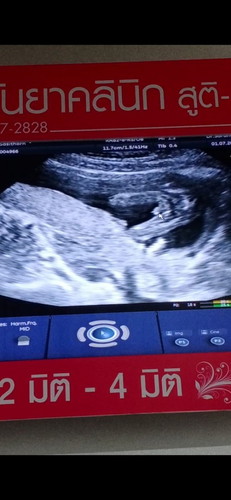

เราไปซาวมาค่ะ ตอน16+5 เหนเพศน้อง หมอบอกชาย เราอยากถามว่า ทำไมคนอื่นซาวใต้หว่างขาน้องเหนแค่จุ้ดจู๋โด่

เราไปซาวมาค่ะ ตอน16+5 เหนเพศน้อง หมอบอกชาย เราอยากถามว่า ทำไมคนอื่นซาวใต้หว่างขาน้องเหนแค่จุ้ดจู๋โด่มา แต่ทำไมของเราเหนทั้งจู๋ทั้งไข่เลยคะแม่ #ขอคำแนะนำหน่อยค่ะ